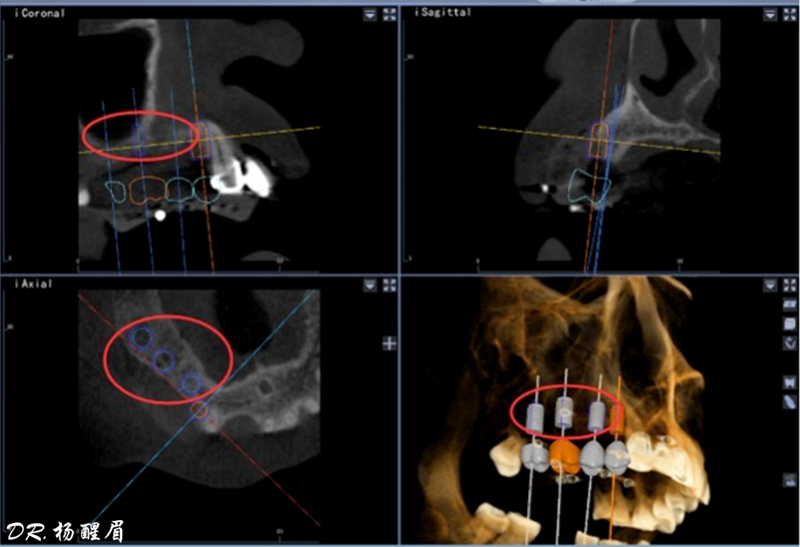

®石膏模型上進行排牙確定患者咬合關系,取放射阻射材料灌于缺牙區(qū),患者戴著處理過的

配準裝置拍攝術前CBCT。

®根據(jù)CBCT中牙冠顯影位置,按照修復引導種植的原則進行方案設計

®使用迪凱爾易植美導航軟件進行方案設計,確定種植體使用方案,以及種植位點,方向和深度

®多顆植體種植方案應盡量保持軸向在同水平線上